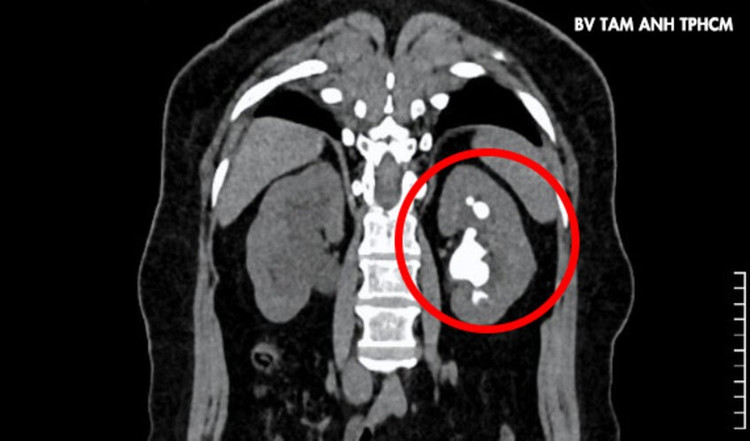

Lên cơn đau quặn thận, bà Trinh, 51 tuổi, ngụ TP HCM đến Bệnh viện Đa khoa Tâm Anh TP HCM khám, bác sĩ phát hiện người bệnh có sỏi cùng lúc ở đoạn trên niệu quản phải, kích thước khoảng 8×10 mm. Thận trái có sỏi kích thước 24×42 mm cùng nhiều sỏi nhỏ ở đài thận trên.

ThS.BS Nguyễn Tân Cương, Phó khoa Tiết niệu, Trung tâm Tiết niệu – Thận học – Nam khoa, cho biết sỏi thận trái có hình dạng san hô lấp đầy các đài thận, nguy cơ nhiễm khuẩn và tổn thương thận một cách âm thầm, người bệnh cần phẫu thuật sớm.

Sỏi san hô cứng, kích thước lớn (màu trắng trong hình tròn đỏ) ở thận trái gây đau đớn cho người bệnh. Ảnh: BVCC